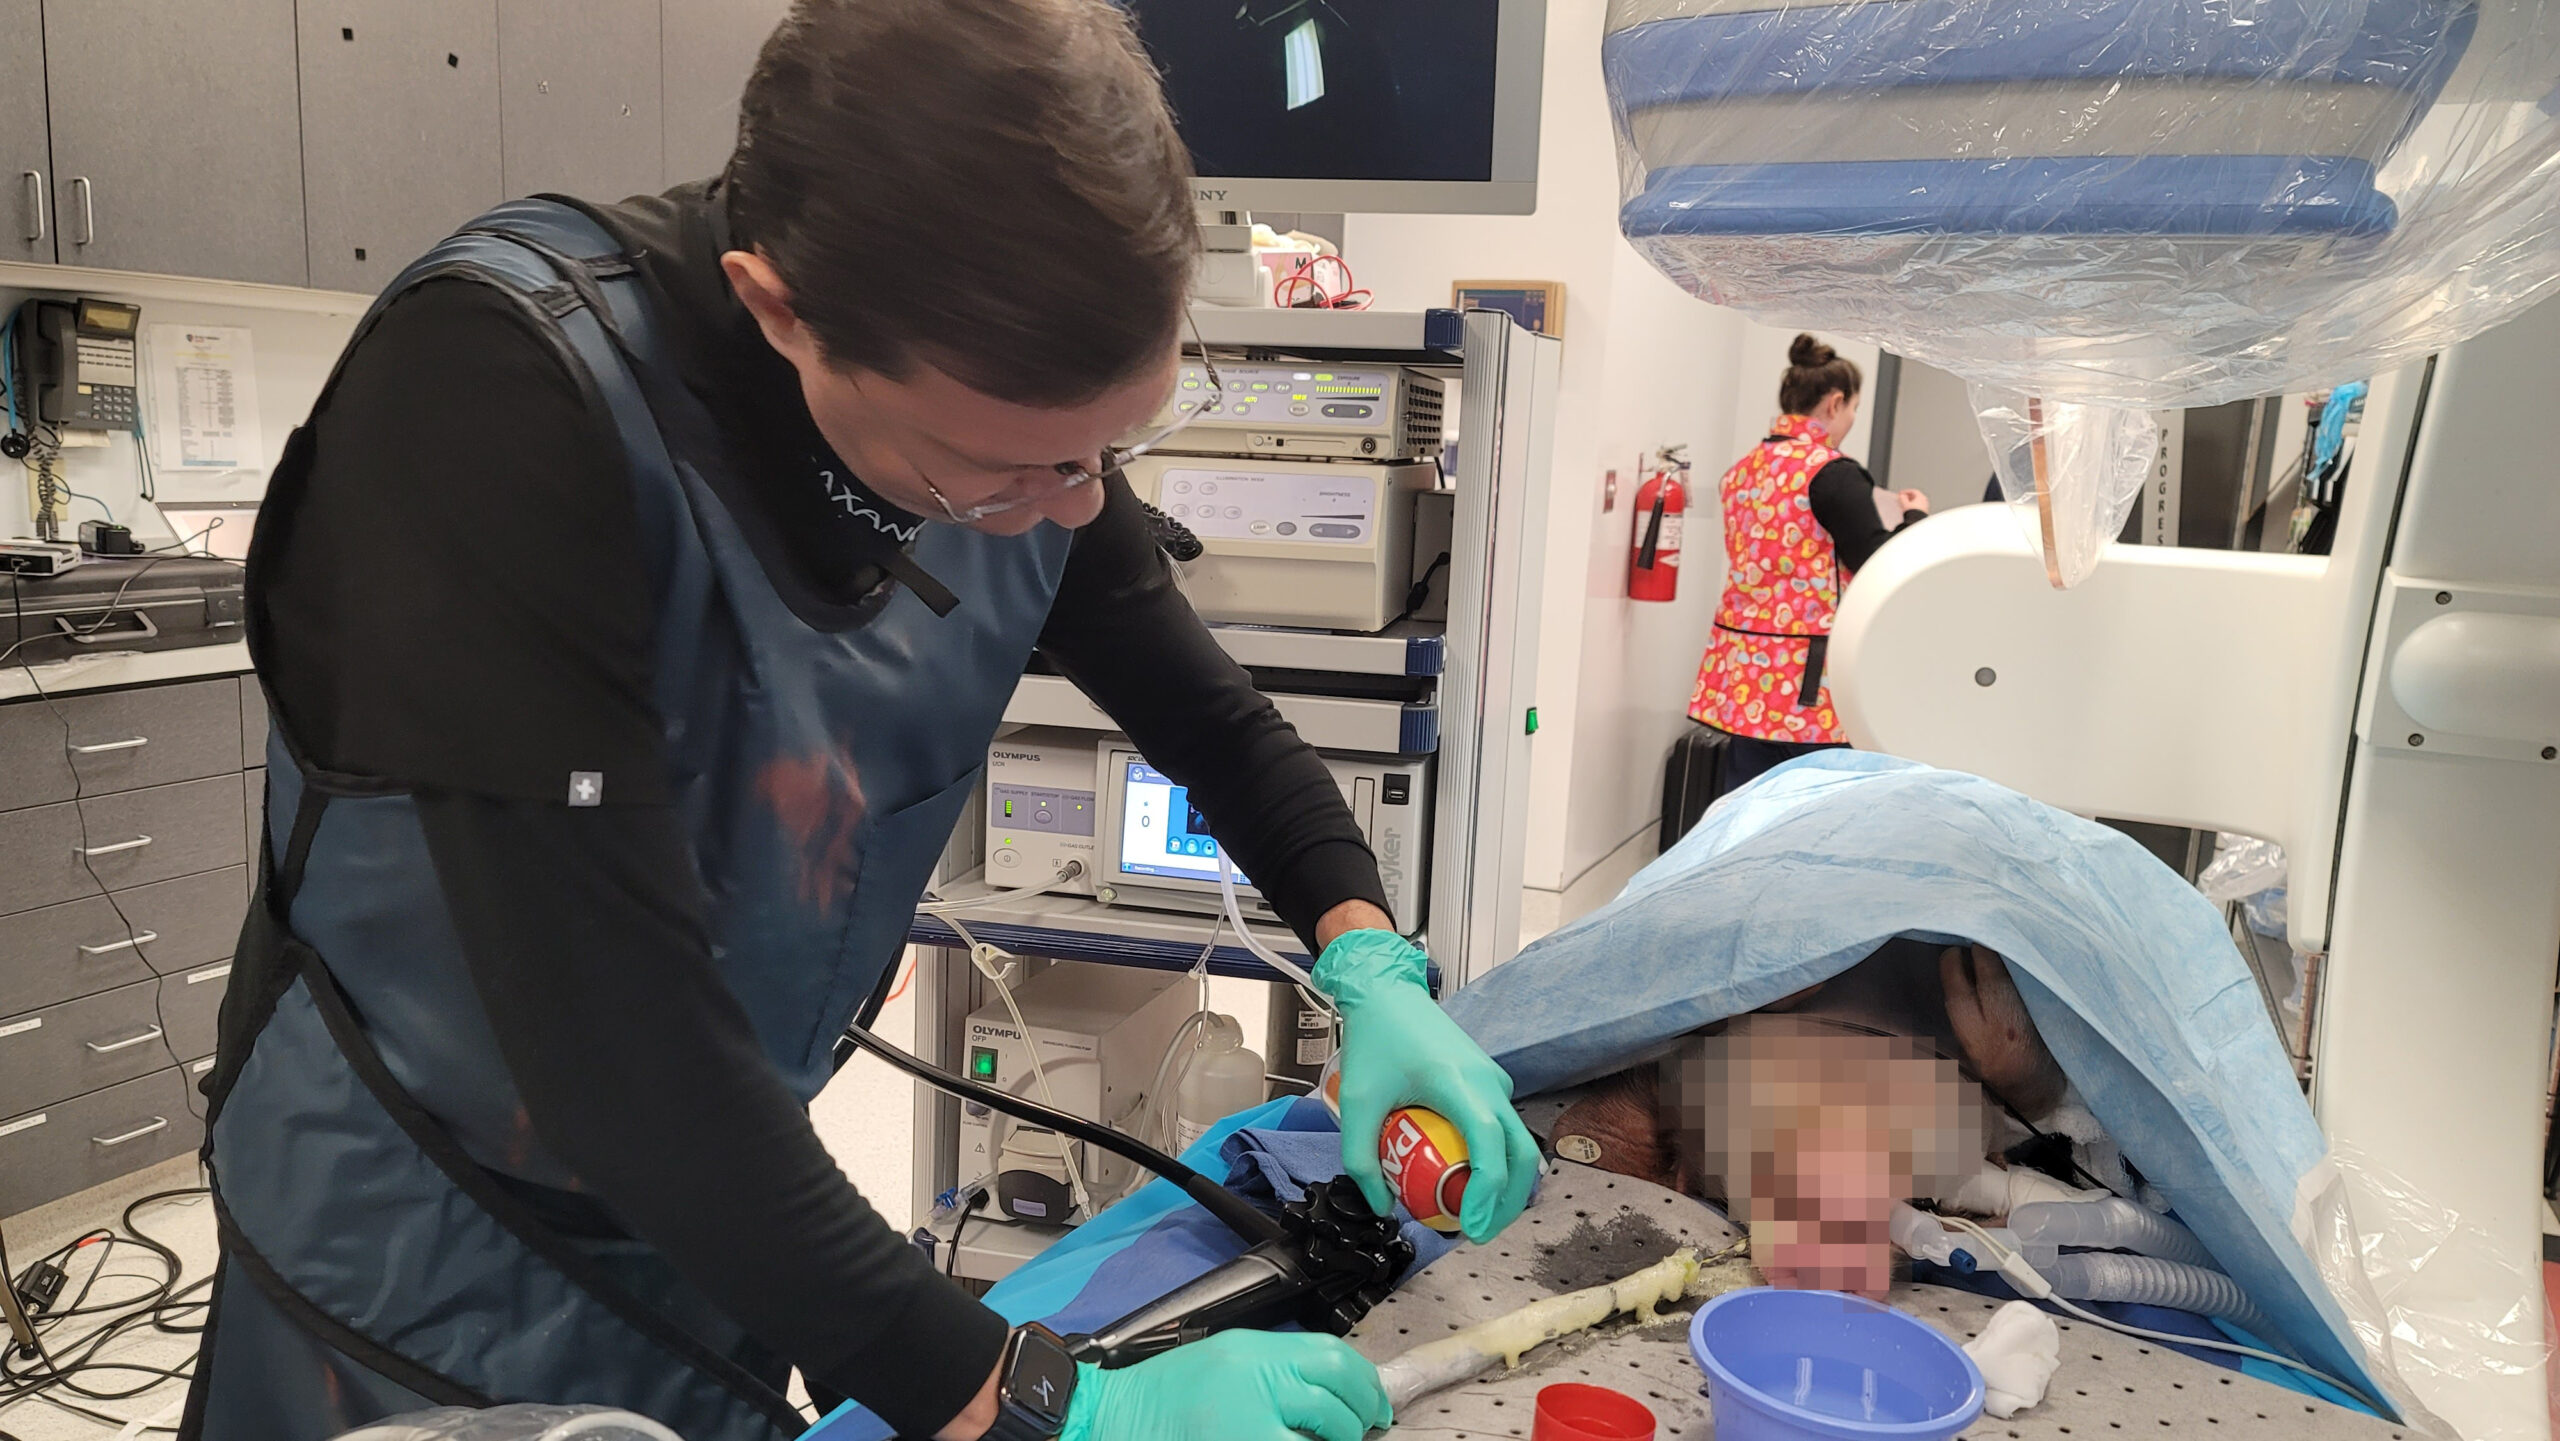

A fully incisionless procedure

The first cut-free endoscopic treatment for diabesity, ForePass ® is able to replicate the most common types of metabolic surgery (Roux-en-Y Gastric Bypass, RYGB, BilioPancreatic Diversion, and Sleeve Gastrectomy). The first version of our product is aimed at RYGB.

Designed to replicate metabolic surgery without any cuts to internal organs. As effective on diabetes and obesity as metabolic surgery in animals.